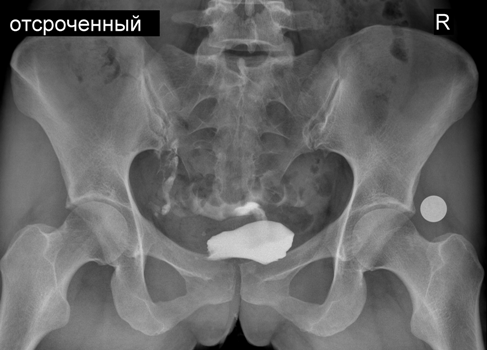

Гистеросальпингография. Непроходимость маточной трубы. Женское бесплодие

Врачом-рентгенологом клиники №1 Витерра Беляево выполнены: укладка пациента, цифровой R-снимок малого таза (обзорный), 2 цифровых R-снимка, оценивающих распределение контрастного вещества и отсроченный (контрольный) цифровой R-снимок.

Протокол: Полость матки небольших размеров, неправильной треугольной формы, без дефектов наполнения, находится в положении антерофлексио.

Левая маточная труба тонкая, извита, проходима на всем протяжении - контрастное вещество свободно поступает в брюшную полость, распространяясь в ней по типу "дымящейся сигареты".

Правая маточная труба не контрастируется.

Тазовое кольцо сформировано правильно, симметрично. В зоне визуализации определяются тени рентгенконтрастных флеболитов, аномалия развития крестцового отдела позвоночника spina bifida posterior S1. Округлая тень артефакта размером 2,1см в диаметре - монета.

Заключение: Рентгенологическая картина непроходимости правой маточной трубы.